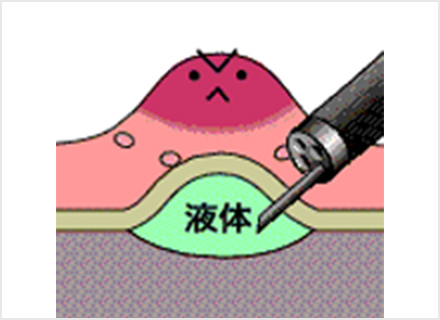

内視鏡的粘膜下層剥離術:ESD(Endoscopic submucosal dissection)

専用の処置具を使いより広範囲に病変を切り取ることが可能な治療法です。切り取られた病変は、最終的に顕微鏡でその組織の様子が確認されます(病理検査)。この方法では、大きな病変をひとかたまりで取り、病理検査でより正確な診断を行うことができます。

ESDは大きな病変も一括して切除可能ですが、手技が煩雑で時間がかかり、出血や穿孔などの併発症が生じる場合があります。ほとんどの場合内視鏡的に止血可能ですが、稀には輸血、開腹手術などを要することがあります。

内視鏡を胃の中に入れ、病変の周辺に切り取る範囲の目印をつける

粘膜下層に薬剤を注入して浮かせた状態にする

マーキングを切り囲むようにナイフで病変部の周囲の粘膜を切る

専用ナイフで病変を少しずつ慎重にはぎ取る

ナイフを使って最後まで剥離する、またはスネアで切り取る

切り取った後の胃の表面に止血処置を施し、切り取った病変部は病理検査に出すために回収する

切り取った病変は顕微鏡による組織検査をして、根治しているかの判断をする

※オリンパス社ホームページ おなかの健康ドットコム より引用